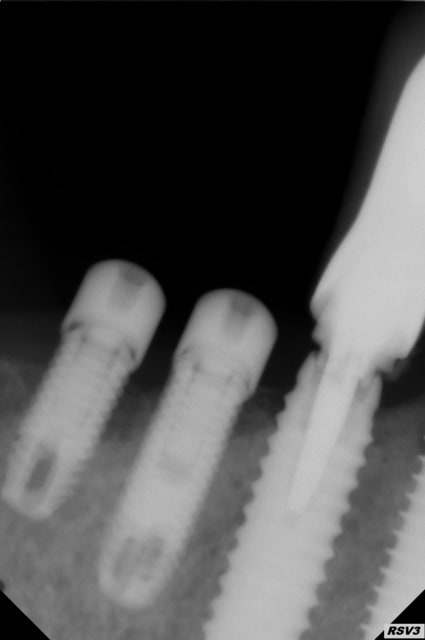

bonjour je vous envoie un cliché qui me semble meilleur que les deux autres afin que vous m aidiez a identifier ces deux implants

Desolé le fichier est tourné de 90° c' est bien la 24 et la 25

1/ ta radio est à la fois floue et à la fois mal centrée, du coup on y voit rien de plus...

3/ pour l'instant je reste persuadé que c'est un Zimmer au col explosé, sur lequel on a "bidouillé" un truc pour pouvoir mettre une vis de cicat (regarde ta radio, il reste un peu d'espace dans le filetage de l'implant en 14 et quasi plus du tout sur celui en 15)...et pour une vis, le filetage et un appuis sur ce qui reste du col suffit à la stabilité

4/ la thèse des cols explosés et du bidouillage est d'autant plus plausible quand on voit ce qu'il y a sur la 13...avec une richemond scellée dans l'implant

5/ vu la périimplantite sur ces 2 implants, amha la solution la plus sage...est de virer tout çà!!! et même celui en 13 qui n'a certainement plus de filetage interne...

mais pour connaître le fin mot de l'histoire et mettre un nom sur ces implants...une bonne radio et des photos stp...